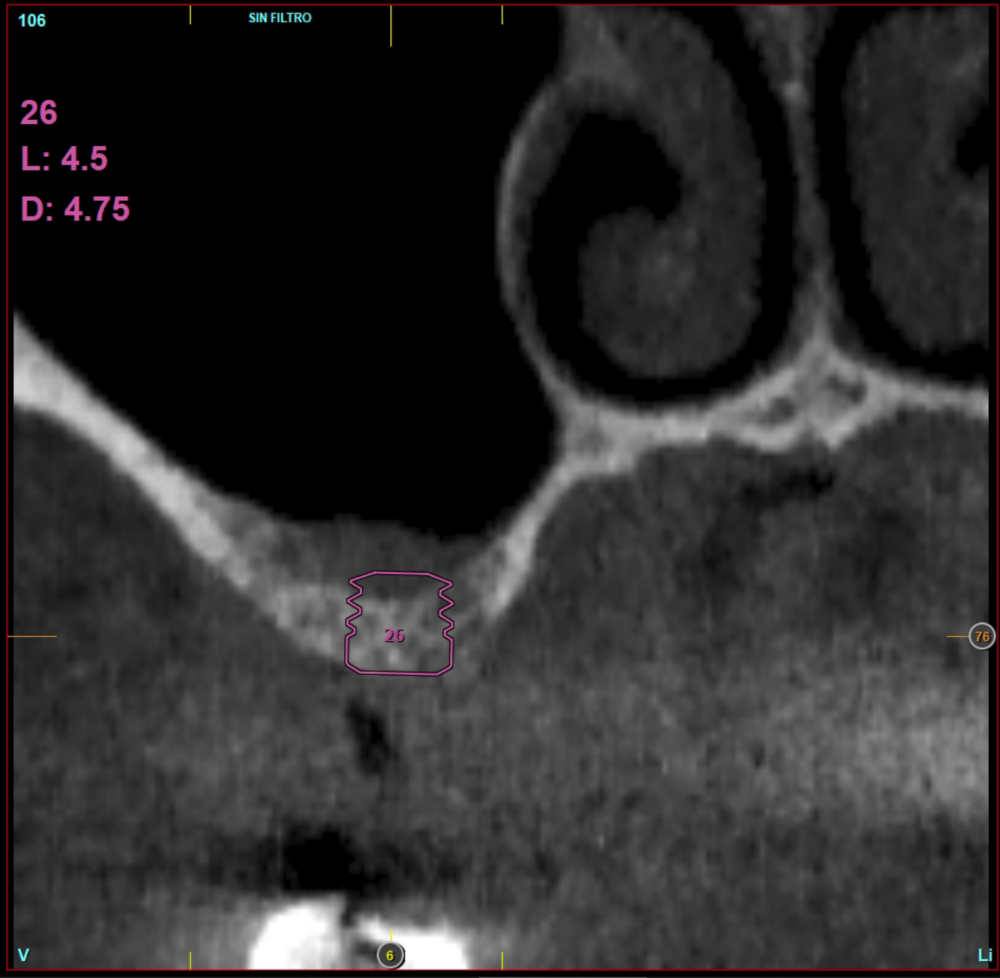

In all cases, a diagnosis was made based on study models, intraoral examination of the patient and performing a Cone-beam analysed using the specific BTI-Scan 3 software (Biotechnology Institute, Vitoria, Alava, Spain).

Patients attend subsequent check-ups performing a control Cone-Beam after 5 months (before loading the implant) and after one year of the load, performing a new measurement in these images to analyse the bone gain and the maintenance of the same. In these check-ups, data are collected on prosthetic complications or crestal bone loss in these patients, as well as possible failures.

Ten patients who met the inclusion criteria were recruited, in which 20 implants were inserted. Three of them were women with an average age of 72 (+/- 6 years). None of the patients were smokers at the time of surgery and did not have any active periodontal disease. The majority of the implants diameter included in the study was 5 mm (60%), followed by 4.5, 5.5 and 4.75 mm (13.33% each). The predominant length was 5.5 mm (86.6% of the cases), with 13.4% of the remaining implants with a length of 4.5 mm. The most common positions were for the second molars (molars 27 and 17) representing 55% of the cases.

The mean height of the residual bone volume was 3.1 mm (+/- 0.3 mm with a range of 3-4 mm). In all cases, transcrestal sinus elevation was performed, with particulate autologous bone obtained from milling the neo alveolus generation zone for implant insertion, being the average of this elevation above the apex of the implant of 2.8 mm (+/- 0.99 range 1.9 -5 mm). In the CT control scan after one year of inserting the studied implants, the bone gain achieved was maintained, no decrease in the volume gained was observed, only three cases showed a decrease of between 0.4 and 0.5 mm of the initial volume at the end (Table).

Figures 2-19 show one of the cases included in the study.